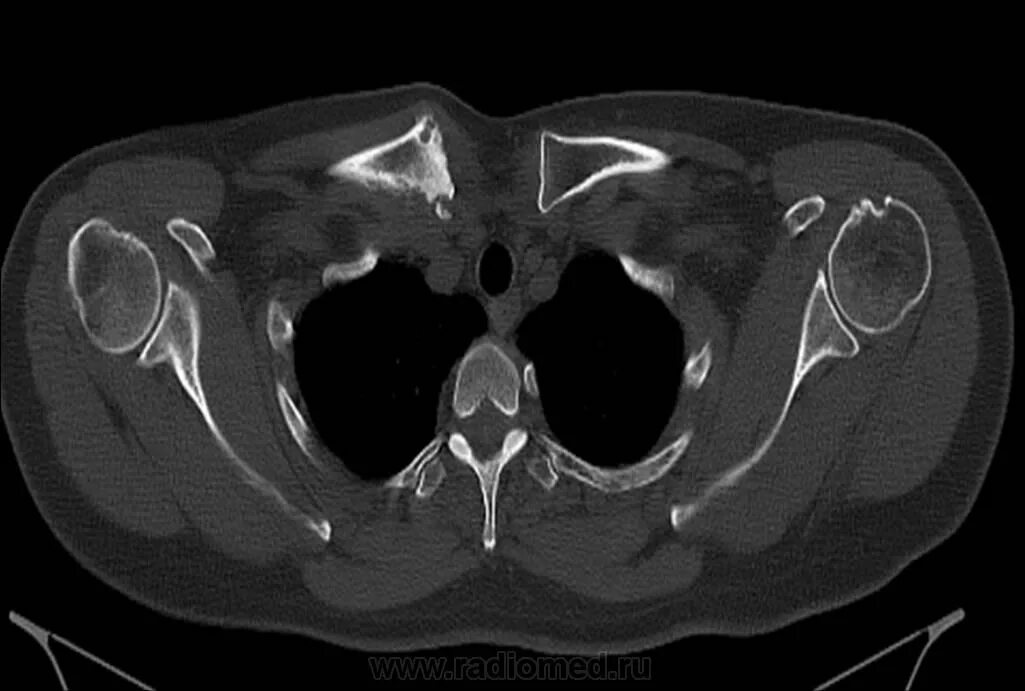

Грудино ключичная артрит